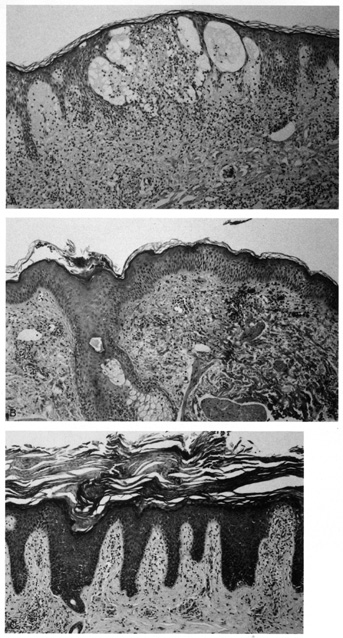

Lesions of molluscum contagiosum often affect the periorbital and lid skin as 1- to 3-mm domeshaped papules with a small central dell. This large pox virus multiplies in the cytoplasm, and, histologically, homogeneous purple intracytoplasmic inclusion bodies (molluscum bodies) are seen in an acanthotic epidermis (see Fig. 7).

Fig. 7. Molluscum Contagiosum—A. Umbilicated lesions typical of molluscum contagiosum on the upper lid of a child. Infection near the edge of the lid may cause a toxic follicular conjunctivitis. B. Low-power photomicrograph demonstrating crater shape of excised lesion (hematoxylin and eosin stain). C. High-power photomicrograph illustrating the large clumps of eosinophilic viral inclusions in the epithelial cells (“molluscum bodies“) (hematoxylin and eosin stain). (Photos courtesy of William Morris, M.D.)

Verruca vulgaris (warts) are caused by a variety of papilloma viruses and may present as small papules with a digitated surface or elongated filiform warts around the eyes. Histologically, they demonstrate varying degrees of massive papillomatosis, hyperkeratosis, and acanthosis with parakeratosis and collections of serum in the stratum corneum at the tips of the digitations (Fig. 8). In early warts, the keratinocytes in the granular layer and just beneath the granular layer are vacuolated with condensation and clumping of dark-staining keratohyaline granules and occasional eosinophilic inclusion bodies in the nuclei.

Fig. 8. Verruca Vulgaris—A. Low-power photomicrograph illustrating papillomatous growth with a fibrovascular core, hyperkeratosis, and acanthosis (hematoxylin and eosin stain). B. High-power photomicrograph demonstrating intranuclear viral inclusion (black arrow) (hematoxylin and eosin stain). (Photos courtesy of William Morris, M.D.)